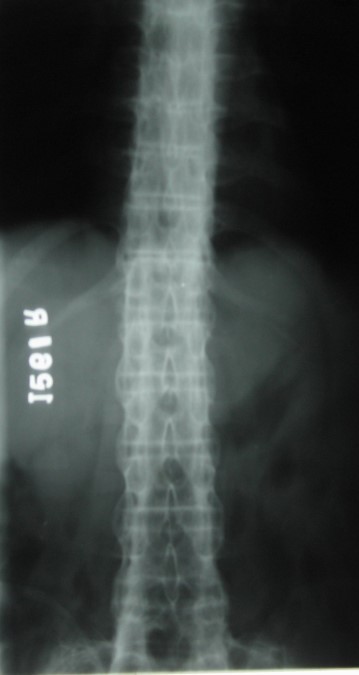

A S Bamboo spine